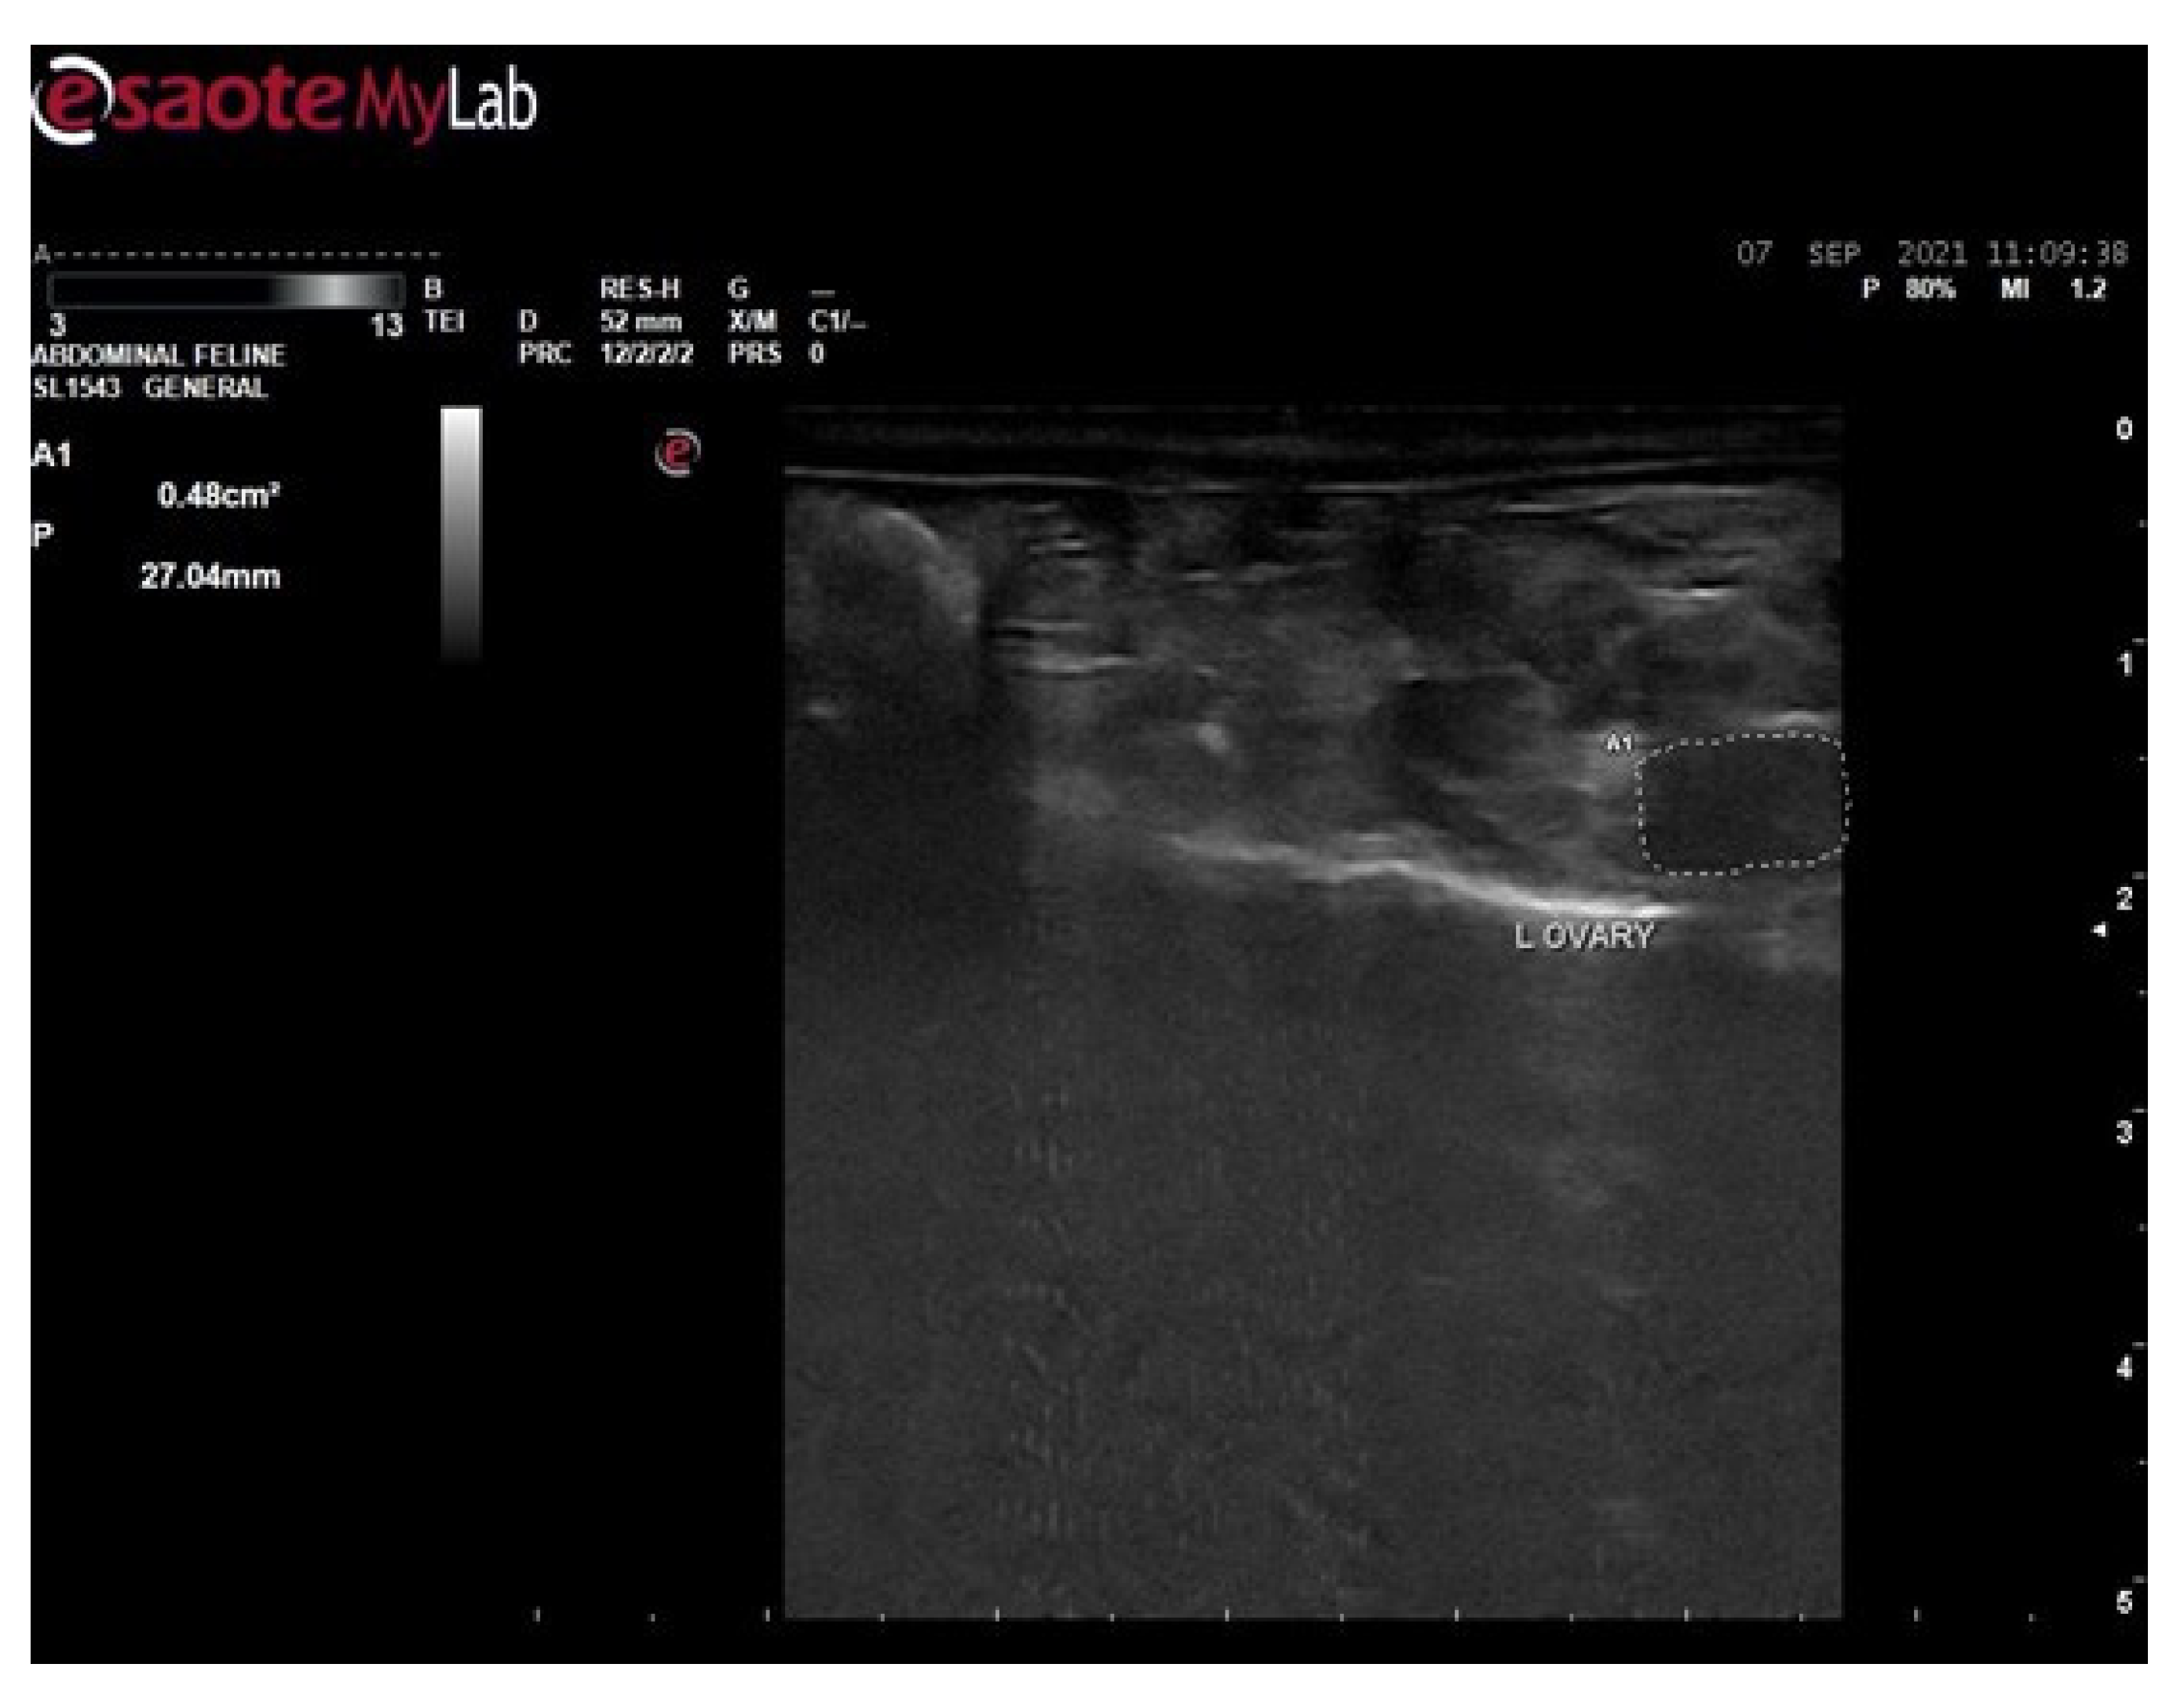

3.6. Ultrasound Examination for Diagnosis of PCOS

3.6.2. Ultrasound Examination of Female Rats of Disease Group